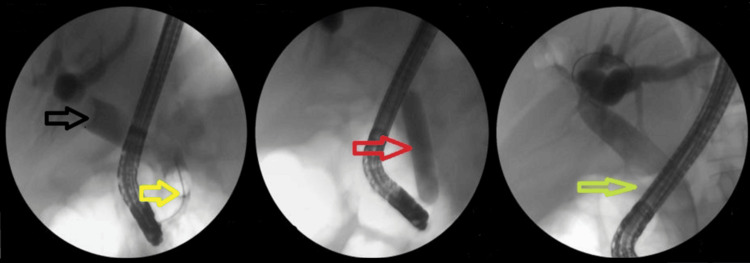

Notably, the majority of difficult stones were cleared in the first session using EPLBD. The overall success rate of EPLBD with endoscopic sphincterotomy was 607/682 (89%). Only 29/190 (15.2%) of cases of EPLBD procedures were not attempted upfront due to narrow lower ends or strictures (Figure 2). In these cases, stenting was performed first, followed by other modalities in subsequent sessions.

The addition of ML to EPLBD and endoscopic sphincterotomy resulted in an overall success rate of 625/682 (91.6%). Figure 3 illustrates ML used in a patient. The addition of ESWL (Figure 4) resulted in an overall success rate of 638/682 (93.5%), and the addition of EHL resulted in an overall success rate of 650/682 (95.3%) for the endoscopic removal of stones (Figure 5).